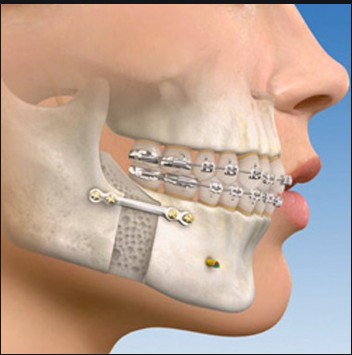

Orthognathic surgery is also known as corrective jaw surgery Is a surgery designed to correct conditions of the jaw and face related to Structure, Growth, Sleep Apnea, TMJ disorders, Malocclusion problems owing to skeletal disharmonies, or other orthodontic problems which cannot be easily treated with braces.This surgery is also used to treat congenital conditions such as cleft palate.he main goals of orthognathic surgery are to achieve a Correct bite, an Aesthetic face, and an Enlarged airway for easy breathing.